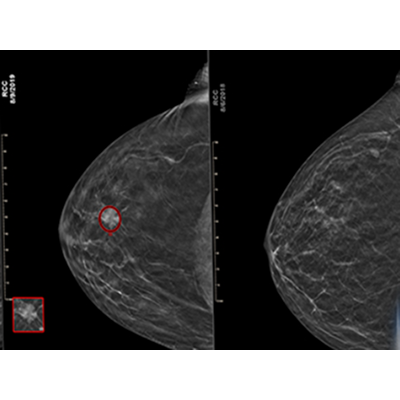

This next-generation AI solution, trained using advanced deep learning convolutional neural networks (CNN), offers advancements in cancer detection and specificity, achieving a 6.3% improved area under the receiver operating characteristic curve (AUC) over prior version, significantly improving the identification of hard-to-find and aggressive cancers while reducing false positives. This fourth-generation version introduces an option for clinicians to incorporate a prior exam into a current exam’s analysis.

Uncovers hidden cancers feared the most while reducing False Positives.

improvement in finding hard-to-find cancers†

improvement in cases with no marks†